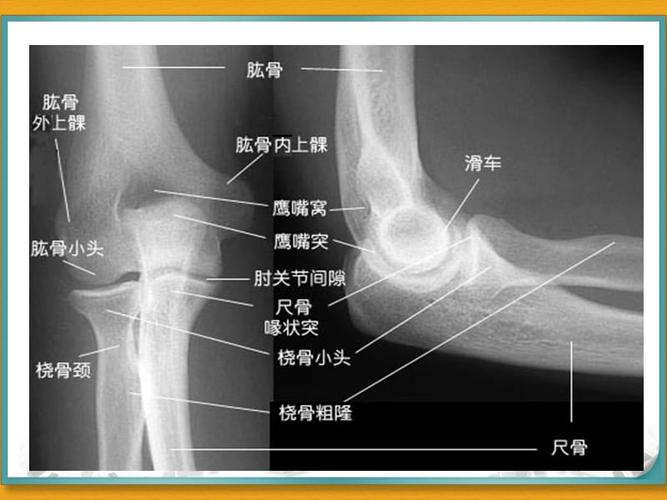

x线高清图谱|精致肘关节解剖

2019--8-26 肘关节x线解剖学